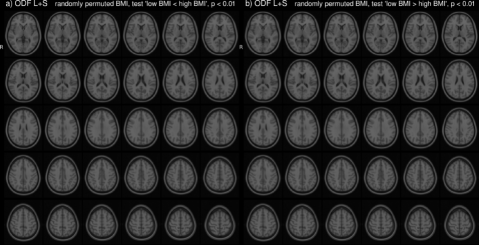

In the HCP dataset, ODFs correlate strongly with the demographic variable BMI. As expected, the ODFs negatively correlate (Fig. 7b) with BMI, indicating a loss of anisotropy with increasing BMI (Fig. 5a,b). This result is consistent with the well-established negative association between global white matter integrity and physical obesity (Mueller et al., 2011; Stanek et al., 2011; Verstynen et al., 2012; Gianaros et al., 2013; Verstynen et al., 2013). The fiber directions (Fig. 8a,b) identified from can be used to perform tractography (Fig. 8c,d). Resulting tracts (Fig. 8c,d) show a pronounced loss of anisotropy in the corticospinal tracts, the optic radiations and the right superior longitudinal fasciculus. These results are corroborated by the existing methods TBSS (Fig. 9a,b, S2a,b), Connectivity-based fixel enhancement (Fig. 9c,d, S2c,d) and local connectometry (Fig. 9e,f, S3a,b). The volume of positive findings of correlation with BMI is largest when using the full ODF information with the ODF approach (Fig. 9). In addition, in a test of specificity, no voxels are found to correlate with randomly permuted BMI (Fig. S4).

None of the above methods however capitalizes on the full ODF information. This in contrast to the approach presented in this paper. The ODF approach indeed identifies a larger volume of significant findings (227 cm3) than the existing methods tested here (TBSS 17 cm3, Connectivity-based fixel enhancement 15 cm3 and Connectometry 212 cm3, Fig. 9b,d,f,h,j). That is, by analyzing the full ODF information and not reducing the dimensionality of the diffusion data, as is commonly done, the ODF approach is able to pick up on smaller significant changes, better grasping the full extent of the significant findings. Limitations on computational power and diffusion acquisitions (e.g. DTI) which inspired the data reduction of older methods no longer exist. It is hence advisable to maximize the amount of information included in the analysis as in the approach presented here.